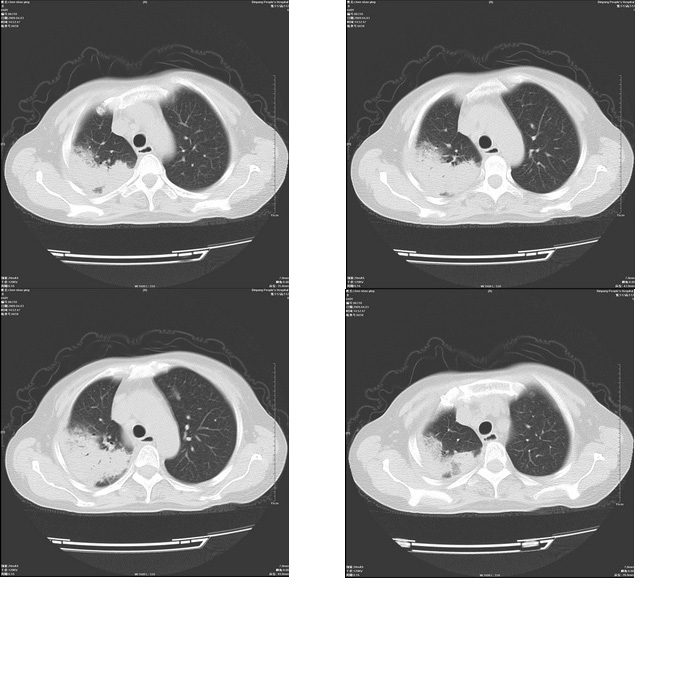

右上肺后段实变影,内见支气管气象,肺门未见软组织肿块,气管前方有肿大淋巴结。左下肺见多个类圆形结节影。考虑:1.右上肺后段大叶性肺炎,需进一步检查病原体种类,应多询问病史,条件许可考虑做纤支镜检查2.左下肺结节影性质待定

右上肺炎 左侧支扩伴感染 结节影抗炎后复查

考虑右上肺后段大叶性肺炎不除外结核,伴双肺结节播散灶,希定期复查。

右肺于酪性肺炎并左肺播散。

考虑两肺继发性肺结核(右肺上叶干酪性肺炎?)。

考虑两肺继发性肺结核(右肺上叶干酪性肺炎)。

右肺干酪性肺炎并左肺播散。

右肺片状实变影,左肺结节影,抗炎及抗捞治疗后病灶进展。

我考虑:不能除外肺炎型肺泡癌可能。建议查痰或活检。